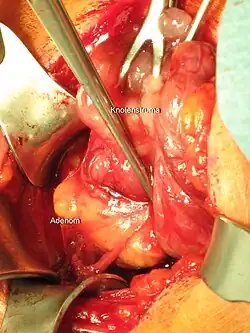

Parathyroidectomy

Parathyroidectomy for parathyroid adenoma | |

Parathyroidectomy is the surgical removal of one or more of the (usually) four parathyroid glands. This procedure is used to remove an adenoma or hyperplasia of these glands when they are producing excessive parathyroid hormone (PTH), a condition termed hyperparathyroidism. The glands are usually four in number and located adjacent to the posterior surface of the thyroid gland, but their exact location is variable. When an elevated PTH level is found, a sestamibi scan or an ultrasound may be performed in order to confirm the presence and location of abnormal parathyroid tissue.

The operation requires general anesthesia (unconscious and pain-free) or local anesthesia (pain-free). The surgeon makes an incision around 2+1⁄2 centimetres (1 inch) long in the neck just under the larynx ("Adam's apple"), and locates the offending parathyroid glands. Preoperative testing using sestamibi scanning can help identify the location of glands. It can also be used to limit the extent of surgical exploration when used in conjunction with intraoperative parathyroid hormone (PTH) monitoring.[3] The particular problem or disease process will determine how many of the parathyroid glands are removed. Some parathyroid tissue must be left in place to help prevent hypoparathyroidism.

The patient is placed in a semi-Fowler position and the neck is extended. An abbreviated Kocher incision is made and the platysma muscle is dissected horizontally. The strap muscles are released off of the thyroid gland. Then the thyroid gland is mobilized and the parathyroid arterial blood supply is suture ligated. The entire parathyroid adenoma is identified and dissected out. Intraoperative PTH monitoring can begin at this time and will show falling PTH levels if the entire adenoma has been resected.[5]